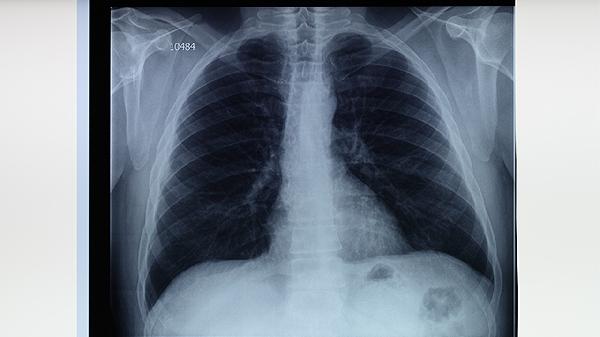

肺结核为什么好发于左肺上叶

肺结核好发于左肺上叶主要与左肺上叶的解剖结构、通气功能及淋巴引流特点有关。肺结核的发病部位受支气管分支角度、局部氧分压、重力作用等因素影响,左肺上叶尖后段支气管走行陡直且通气较差,更利于结核分枝杆菌定植繁殖。